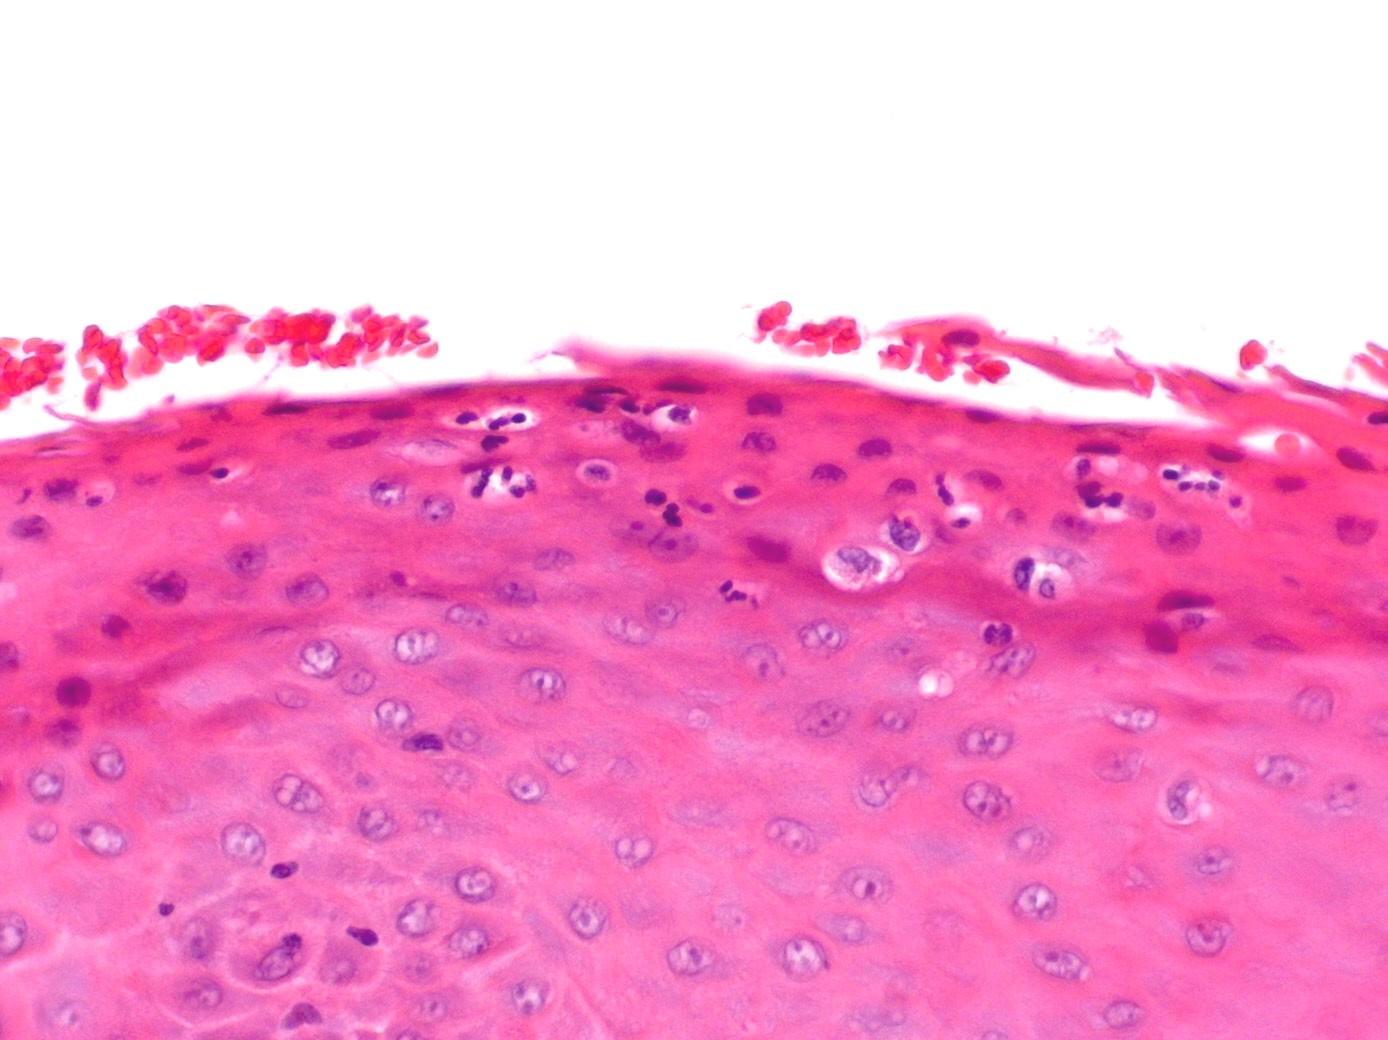

 3. A 30 year old male undergoes biopsy of a white patch on the lateral border of the tongue. Histological examination shows parakeratosis and a band-like layer of cells with clear cytoplasm in the upper stratum spinosum.

Hairy leukoplakia

 Classical histological appearances

 Often candida +++ but lack of inflammation

 Band of clear cells classical

 Should confirm diagnosis by EBV immuno’ or ISH

 Pathognomonic of HIV